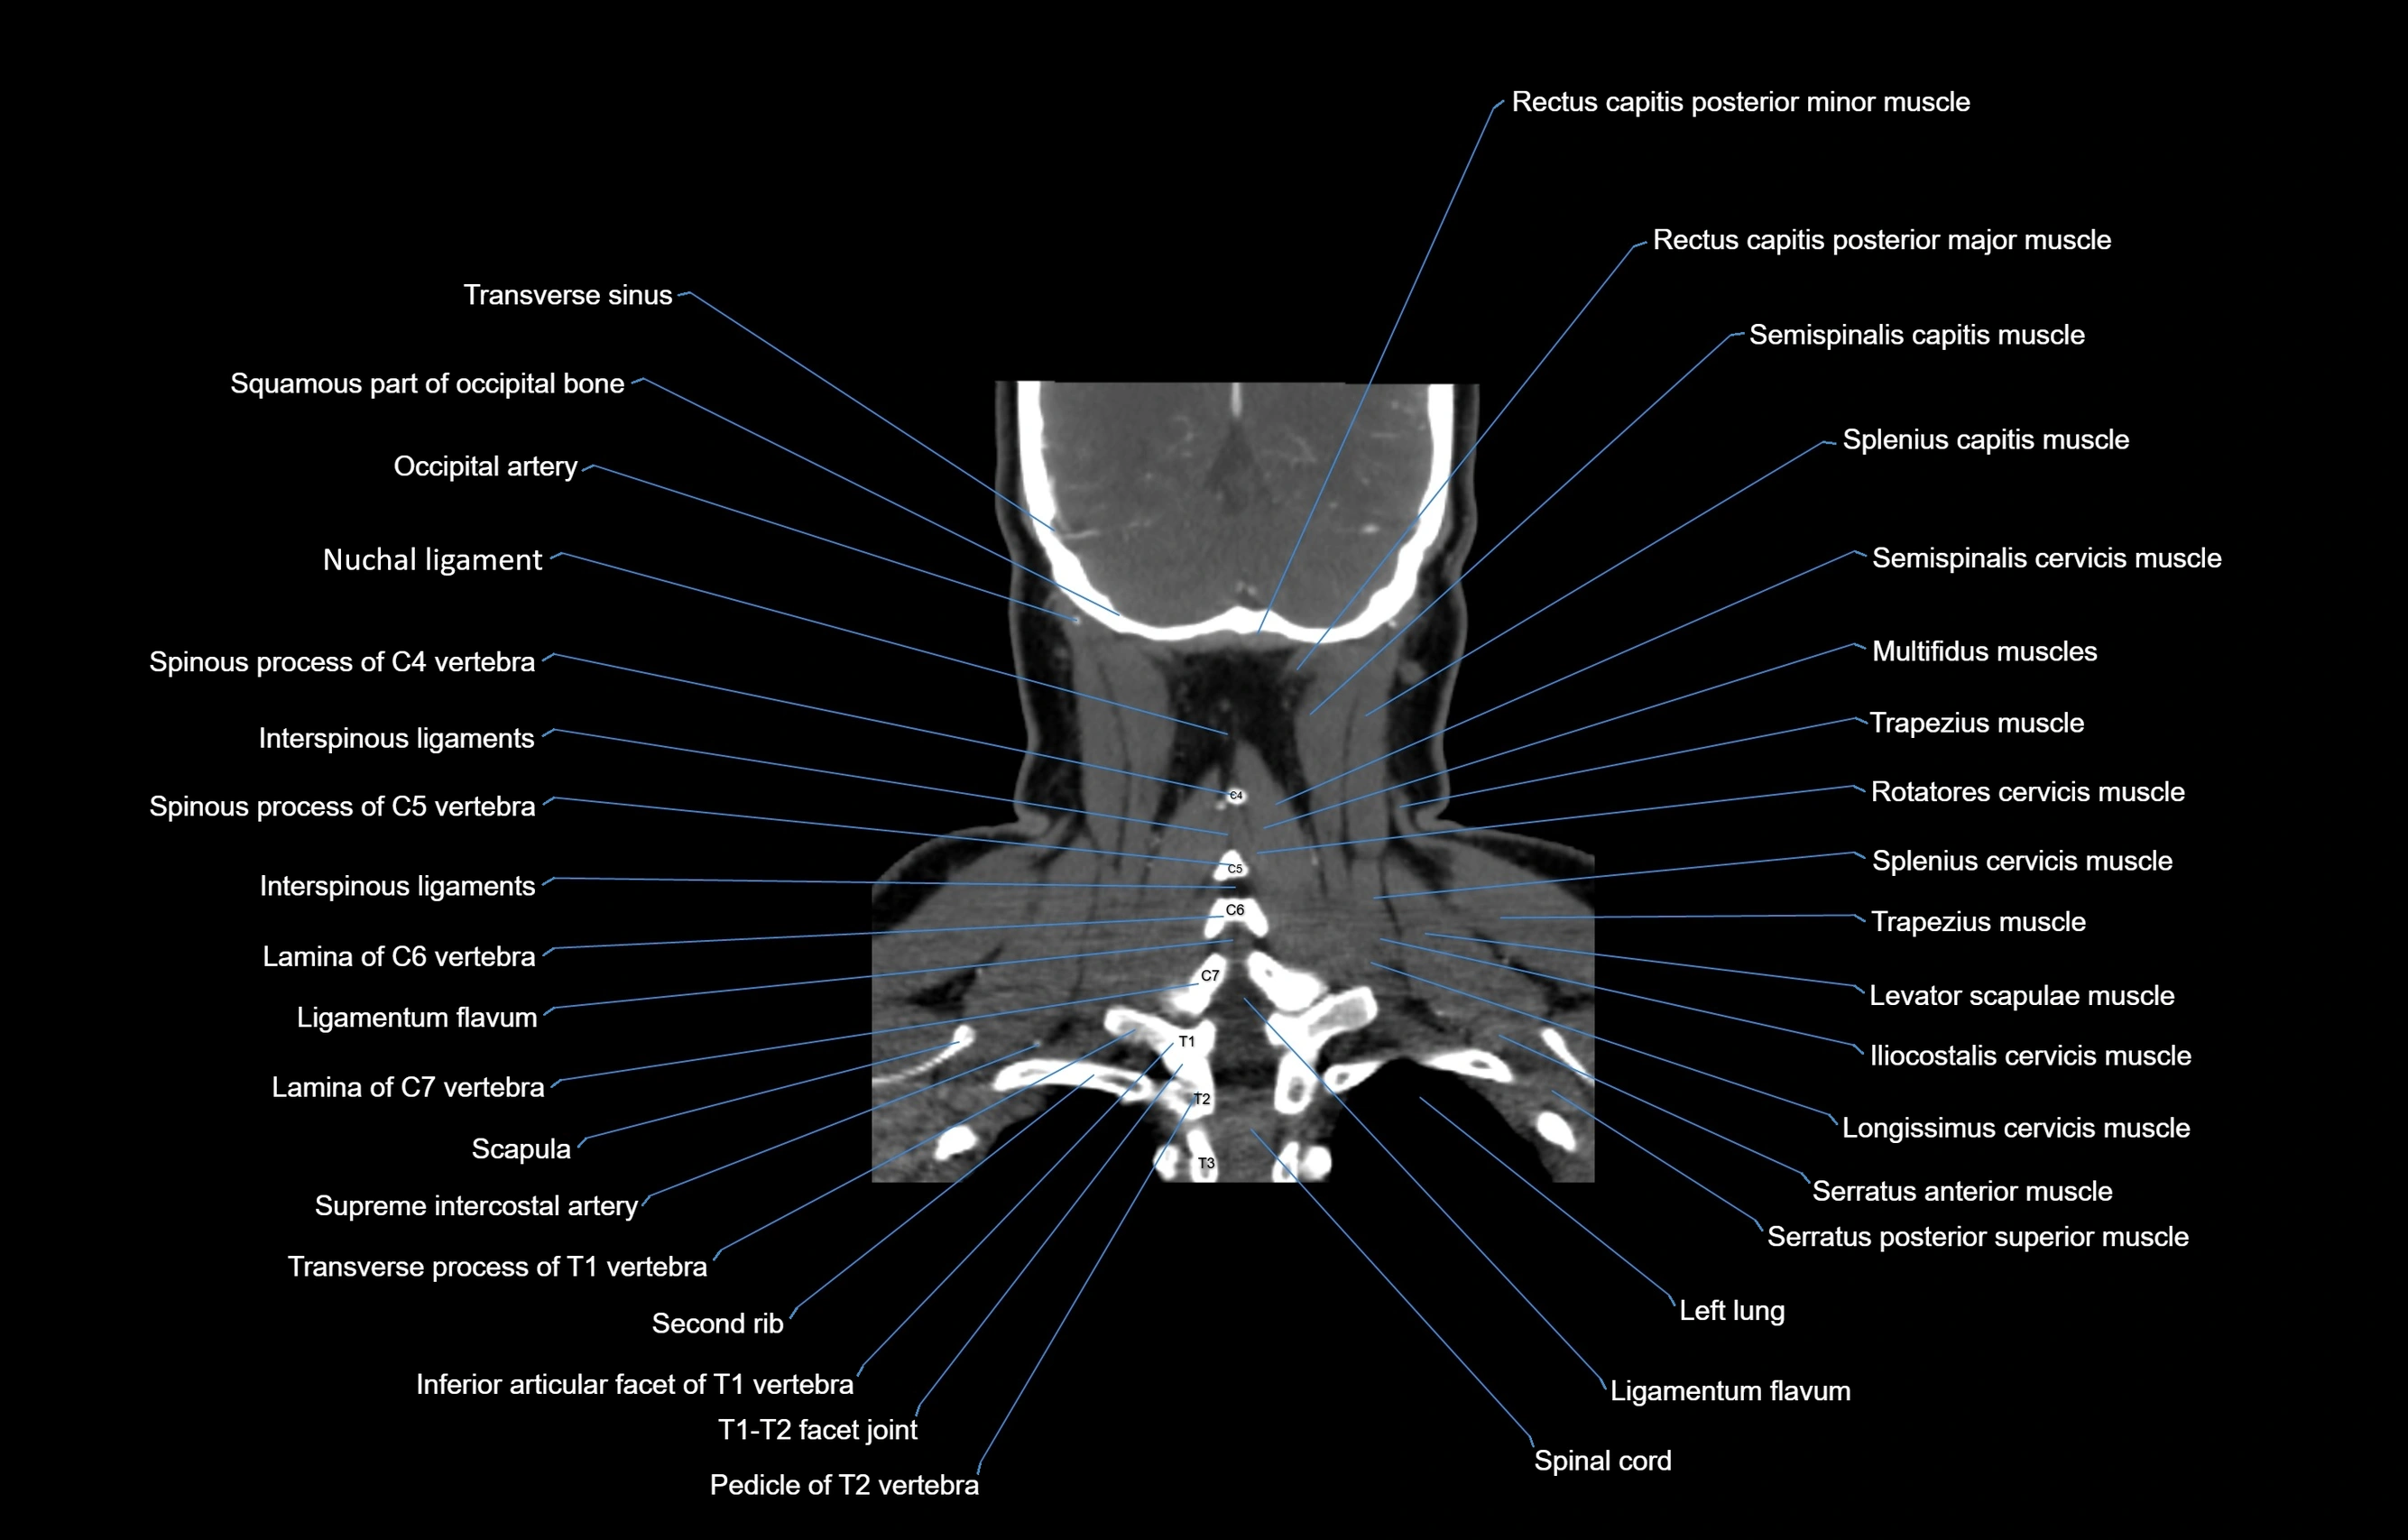

- Interspinous ligament

- Lamina of vertebra

- Ligamenta flava (Ligamentum flavum)

- Longissimus cervicis muscle

- Multifidus muscles

- Nuchal ligament

- Rectus capitis posterior major muscle

- Rectus capitis posterior minor muscle

- Rotatores cervicis muscle

- Rotatores cervicis muscles

- Semispinalis capitis muscle

- Semispinalis cervicis muscle

- Serratus posterior superior muscle

- Spinal cord

- Splenius capitis muscle

- Splenius cervicis muscle

- Trapezius muscle